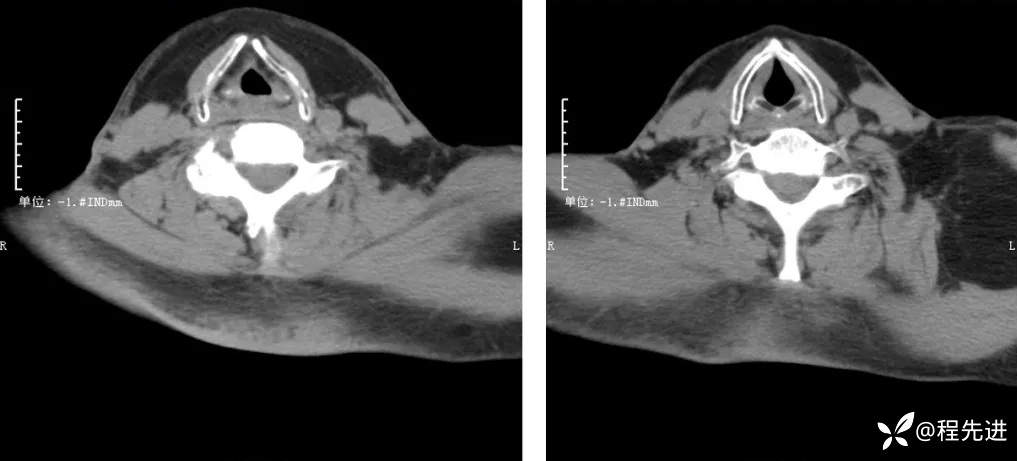

CT检查: